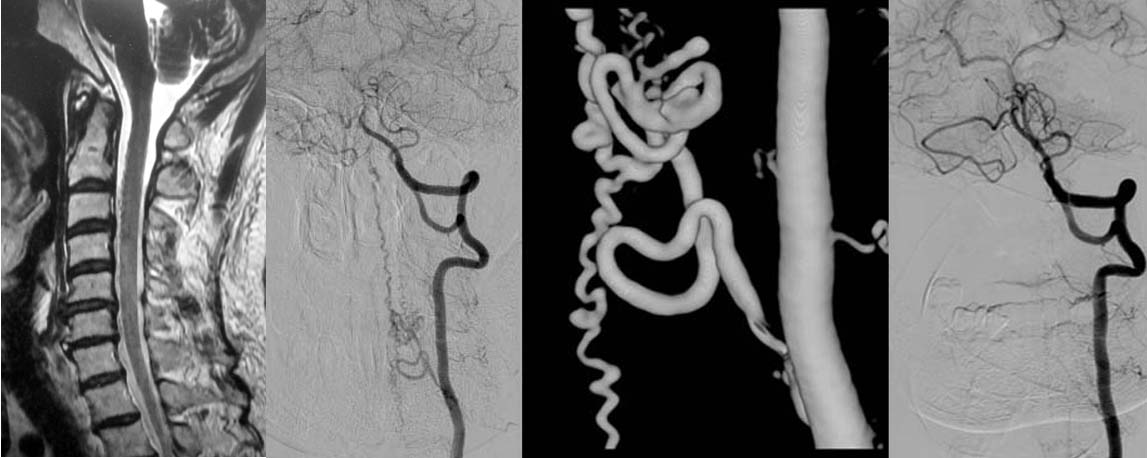

神経所見を診察し、MRI等を施行し脊髄梗塞や出血の診断をします。しかし、脊髄の血管は細かいためMRIだけでは診断は難しく、造影剤を用いたカテーテル検査が必要です。

図1.頚椎MRIでは脊髄の周辺にプツプツとした小さな陰影がみられますが、詳細はわかりません。造影剤を用いたカテーテル検査(左椎骨動脈撮影)では異常血管が描出され、脊髄硬膜動静脈瘻であると診断できます。下記手術を行い、異常血管は消失しました。